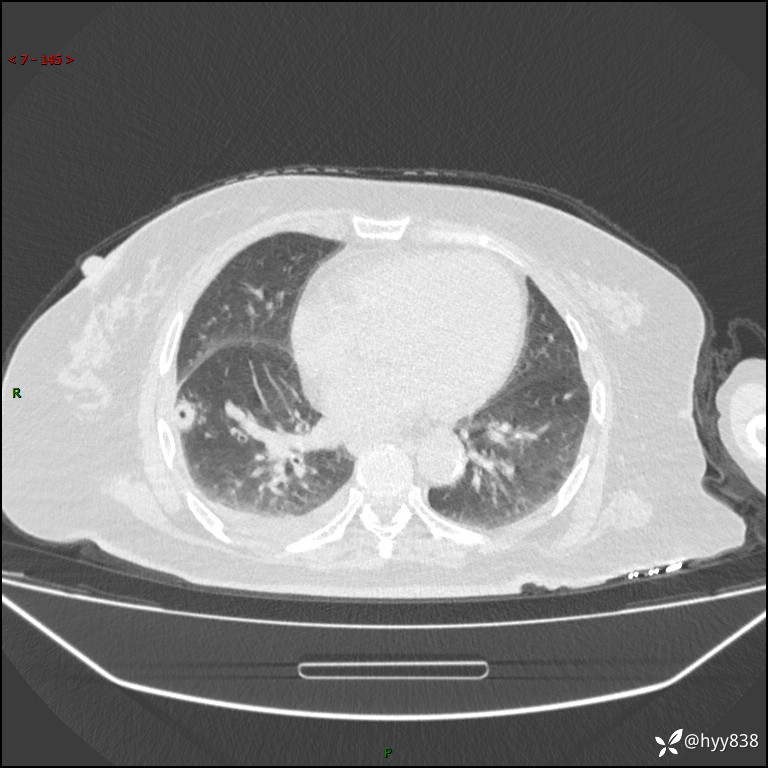

患者性别:女

患者年龄:57岁

简要病史:昏迷入院

临床诊断:昏迷

胸部 CT平扫、